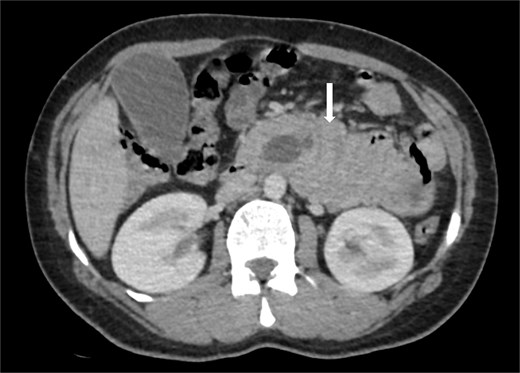

Due to the acute presentation and unavailability of emergency magnetic resonance imaging (MRI), a contrast-enhanced computed tomography (CT) scan of the abdomen was performed with strict fetal protection measures (lead apron, low-dose protocol). The pancreas appeared normal with no signs of inflammation, necrosis, or peripancreatic fluid. Unexpectedly, the scan revealed a duodenojejunal intussusception, likely originating from the fourth portion of the duodenum (D4), involving invagination of a proximal jejunal loop (Fig. 1). A typical pseudokidney sign was observed on sagittal reconstructions (Fig. 2). There was no identifiable lead point such as a mass or polyp. The intussusception was seen tractioning the distal common bile duct, leading to marked extra- and intrahepatic bile duct dilatation (Fig. 3).

Axial contrast-enhanced CT image showing a duodenojejunal intussusception (arrow), originating from the fourth portion of the duodenum and involving invagination of a proximal jejunal loop.